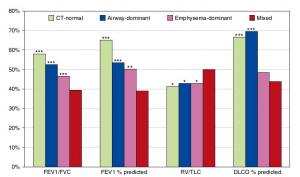

A Mixed Phenotype of Airway Wall Thickening and Emphysema Is Associated with Dyspnea and Hospitalization for Chronic Obstructive Pulmonary Disease.

Radiological Approach to Asthma and COPD-The Role of Computed Tomography.